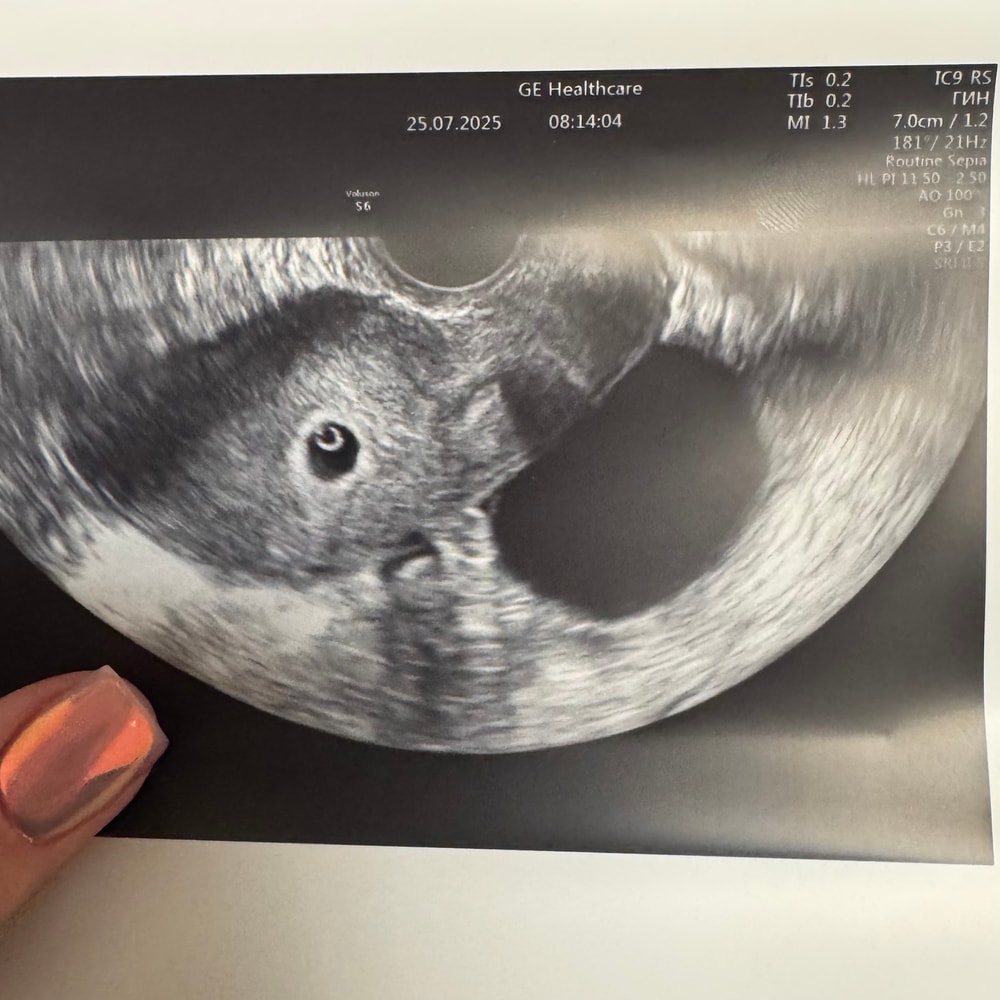

УЗИ в 5,6 недель 🥹

Обследования, узи, анализыМое доброе утро 🥰

Но бусинка моя сидит в середине матки, есть ПЯ, ЖМ и точечка эмбрион. Врач сказала все по сроку и назначила повторное узи через неделю, чтобы послушать сердечко 🙏🏻🥹